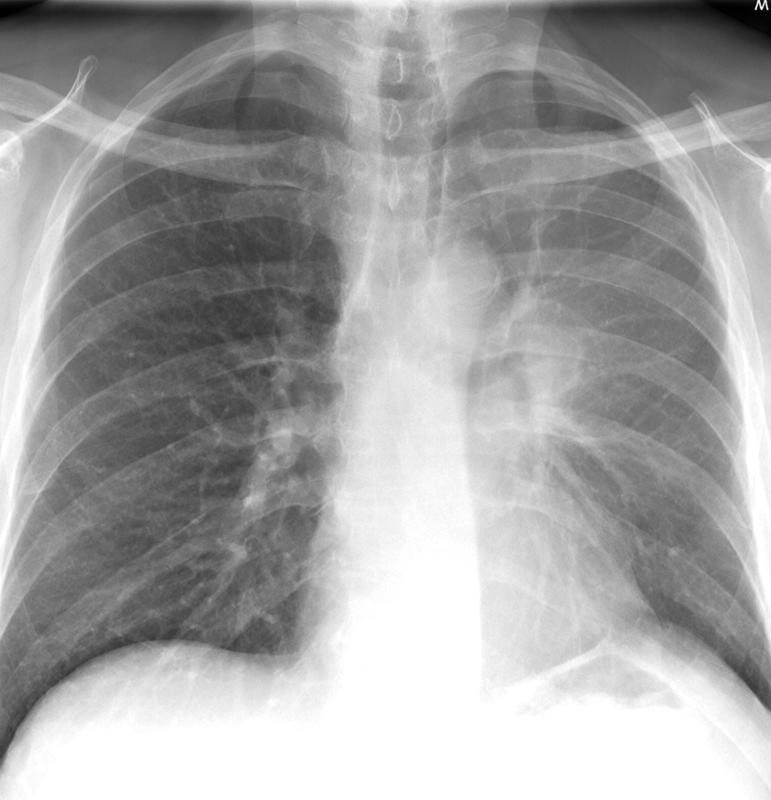

Lobar Collapse

LUL Collapse

LUL collapse Case10